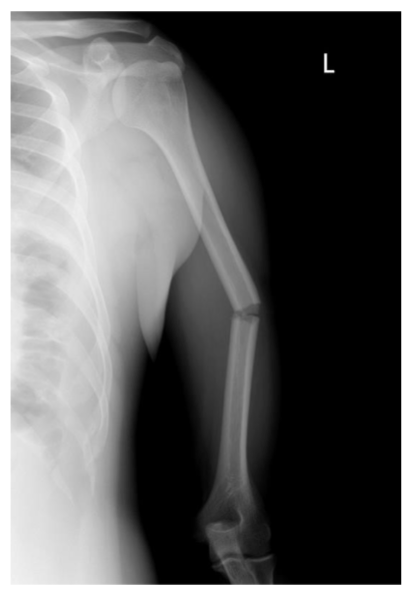

<p>What type of fracture?</p>

What type of fracture?

humeral, mid-shaft, diaphyseal, simple, complete

Humeral Fx

<ul><li><p>proximal 1/3 - immobilize shoulder through traction immobilization or Statue of Liberty cast&nbsp;</p></li><li><p>mid-shaft without significant angulation can use fx brace&nbsp;</p></li><li><p>distal 1/3 - immobilize elbow&nbsp;</p></li></ul><p></p>